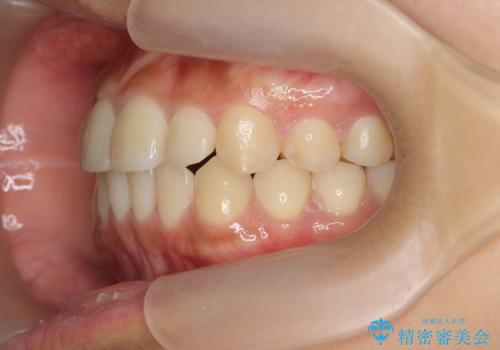

- 前歯のガタつき、上下たがい違いになっている歯並び(クロスバイト)の改善を求めて来院されました。

インビザラインによる矯正治療を行いますが、クロスバイトの改善をワイヤー部分矯正で事前に行うことにより治療期間の短縮する治療計画を立案します。

上下すれ違った噛み合わせはマウスピースでは改善に時間がかかり、またねじれが残ってしまうことも多々見られます。

マウスピース矯正を行う前に、これらの症状の改善の得意なワイヤー部分矯正を行うことで治療期間を短縮し、確実にすれ違いを改善することができます。